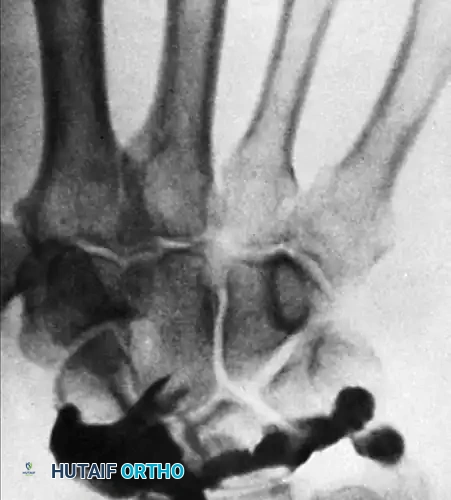

- Fracture Management: Arthroscopically assisted reduction and internal fixation (ARIF) of intra-articular distal radius fractures, scaphoid fractures, and other carpal fractures. It ensures anatomic restoration of the articular step-off and allows for concurrent treatment of associated soft-tissue injuries.

Clinical Pearl: When treating intra-articular distal radius fractures, arthroscopy not only confirms articular reduction but also identifies concomitant TFCC tears (present in up to 40% of cases) and SL ligament tears (present in up to 30% of cases), which are frequently missed on standard radiographs.